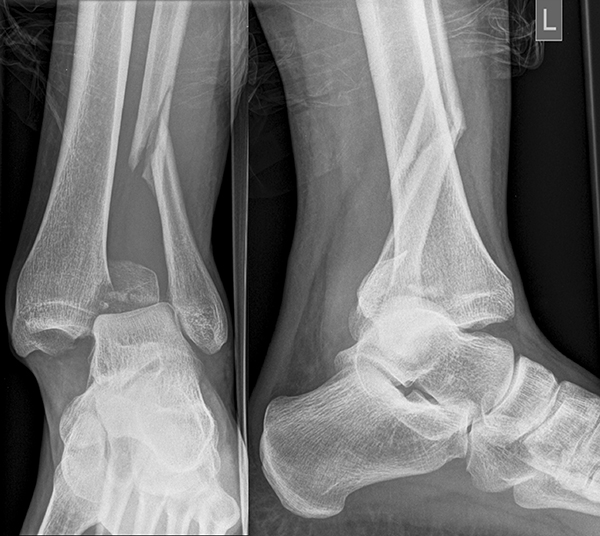

Seit einer Untersuchung von Nelson und Jensen aus dem Jahre 1940 wird allgemein akzeptiert, dass die Indikation zur Osteosynthese des Tibiahinterkantenfragments nur dann besteht, wenn die Größe mehr als ein Drittel (nach zahlreichen Autoren auch ein Viertel) der Gelenkfläche beträgt (Abbildung 15) 25. Dieses bis heute allgemeinakzeptierte Vorgehen basiert auf der Beobachtung von lediglich acht unterschiedlich versorgten Patienten. Seither gibt es keine weiteren klinischen Studien, die dieses Vorgehen stützen. Mittlerweile gibt es allerdings zunehmend Hinweise, dass bei der Versorgung des posterioren Malleolus viele andere Faktoren eine wichtige Rolle spielen 26. Da an der Tibiahinterkante das Lig. tibiofibulare posterius ansetzt (Abbildung 16), wird durch die offene Reposition und Stabilisierung die Integrität und die physiologische Spannung der hinteren Syndesmose rekonstruiert (Abbildung 17). Dies ist entscheidend für die anatomische Reposition der Fibula in der Tibiainzisur.

Gardner et al. konnten beispielsweise zeigen, dass die offene anatomische Reposition der Tibiahinterkante der Stabilisierung mittels Stellschraube überlegen war und gleichzeitig mit einer geringeren Rate an postoperativen Fehlstellungen der Fibula in der CT-Kontrolle einherging 2728. Aus Sicht der Autoren ist prinzipiell die Stabilisierung über eine direkte Reposition indiziert, wenn die Größe des Fragmentes dies erlaubt. Bei gleichzeitigem Vorliegen einer Fraktur des lateralen und/oder medialen Malleolus sollte zunächst die Versorgung der des Tibiahinterkantenfragments erfolgen. Dies erlaubt die radiologische Kontrolle der Reposition und Osteosynthese-Lage, welche durch eine zuvor aufgebrachte Fibula-Platte häufig erschwert ist 29. Dafür werden die Patienten in Seitenlage gelagert. Dies erlaubt die direkte Versorgung der posterioren Malleolusfraktur über einen posterolateralen Zugang 30. Das sehr kräftige Periost wird im Frakturverlauf inzidiert und aus den Frakturspalt entfernt, so kann eine anatomische Reposition erfolgen. Entsprechend der Fragmentgröße erfolgt entweder die Versorgung mittels Drittelrohrplatte in Antiglide-Technik oder eine Zugschraubenosteosynthese. Die Versorgung der Fibula-Fraktur gelingt über den gleichen Zugang. Zur Versorgung des medialen Malleolus wird der Patient auf den Rücken umgelagert. Dies kann bei entsprechender Vorbereitung ohne erneutes steriles Abdecken erfolgen. Durch dieses Vorgehen konnte im eigenen Kollektiv die Notwendigkeit einer Stabilisierung der Syndesmose mit Stellschraube/Tight Rope deutlich reduziert werden.

Posteriorer Malleolus